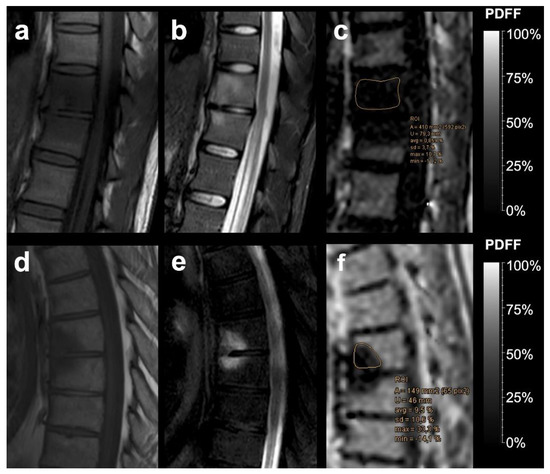

| PDFF | % | 35.29 | 17.15 | 4.28 | 3.12 | <0.001 * |

| PDFFratio | 0.67 | 0.37 | 0.093 | 0.059 | <0.001 * | |